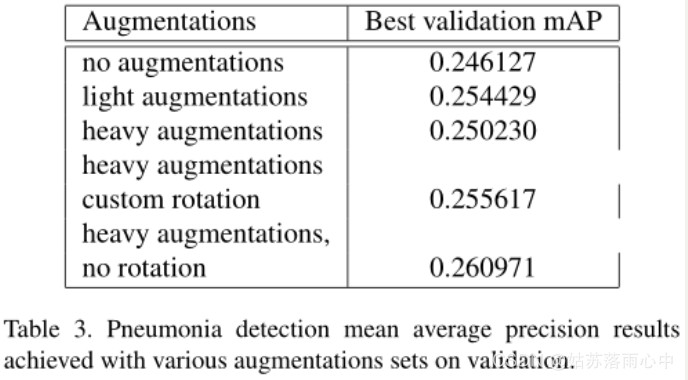

图像数据预处理与图像增强

原始图像按比例缩放为512×512像素分辨率,由于原始的挑战数据集不是很大,因此采用了以下图像增强来减少过拟合:轻微旋转(最多6度);移位,缩放,剪切;水平翻转;对于某些图像,模糊处理,添加噪声,进行伽玛值随机变化;有限提高亮度/伽玛增强量等。